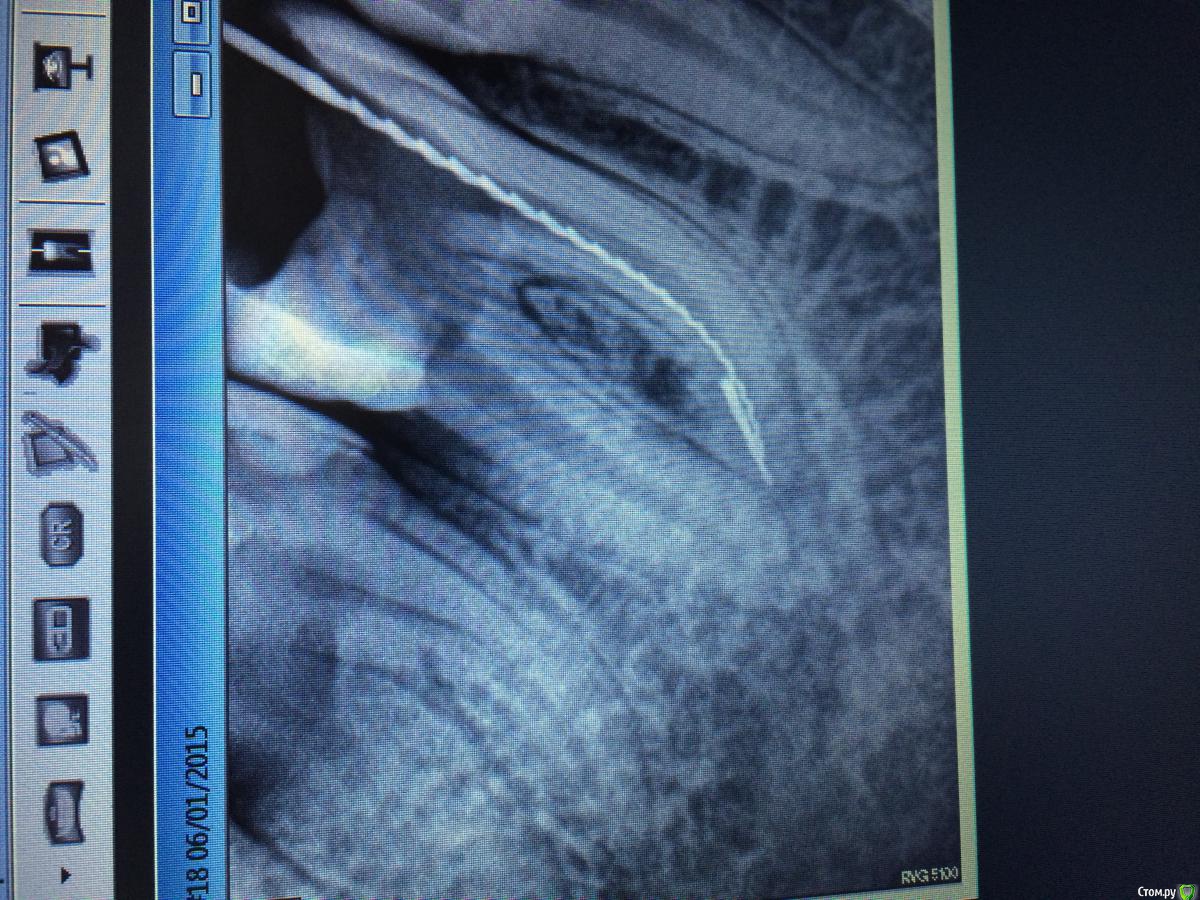

Rashid077 Опубликовано 7 января, 2015 Поделиться Опубликовано 7 января, 2015 (изменено) Здравствуйте. Чем вы вынимаете отломки из каналов если не секрет? втор сним случайн Изменено 7 января, 2015 пользователем Rashid077 Ссылка на комментарий

Rashid077 Опубликовано 7 января, 2015 Поделиться Опубликовано 7 января, 2015 Помогите пожалуйста) есть ли возможность вынуть отломок, 46зуб, файл реципрок 25, зуб ранее был лечен, раскрыт 3 канала 2 нед кальций, при повторной обработке произошел отлом) как быть? Ссылка на комментарий